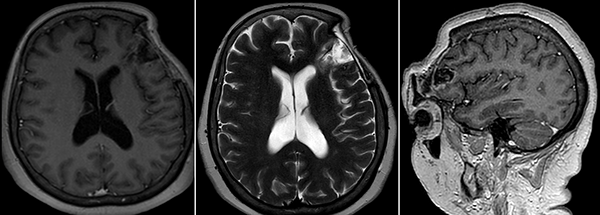

Figura 6. RM de cerebro control a los 4 meses postoperatorio.